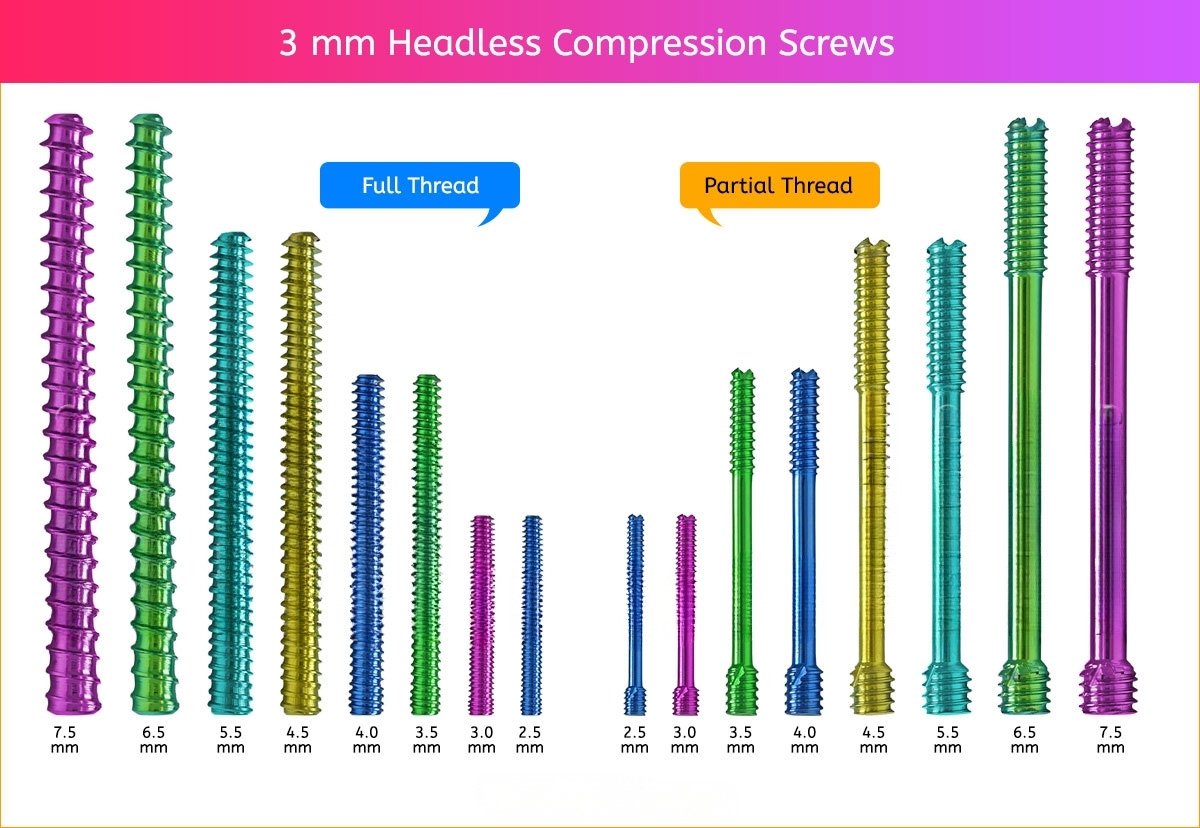

3 mm Headless Compression Screw

3 mm Screws Length

8mm, 10mm, 12mm, 14mm, 16mm, 18mm, 20mm, 22mm, 24mm, 26mm, 28mm and 30mm.